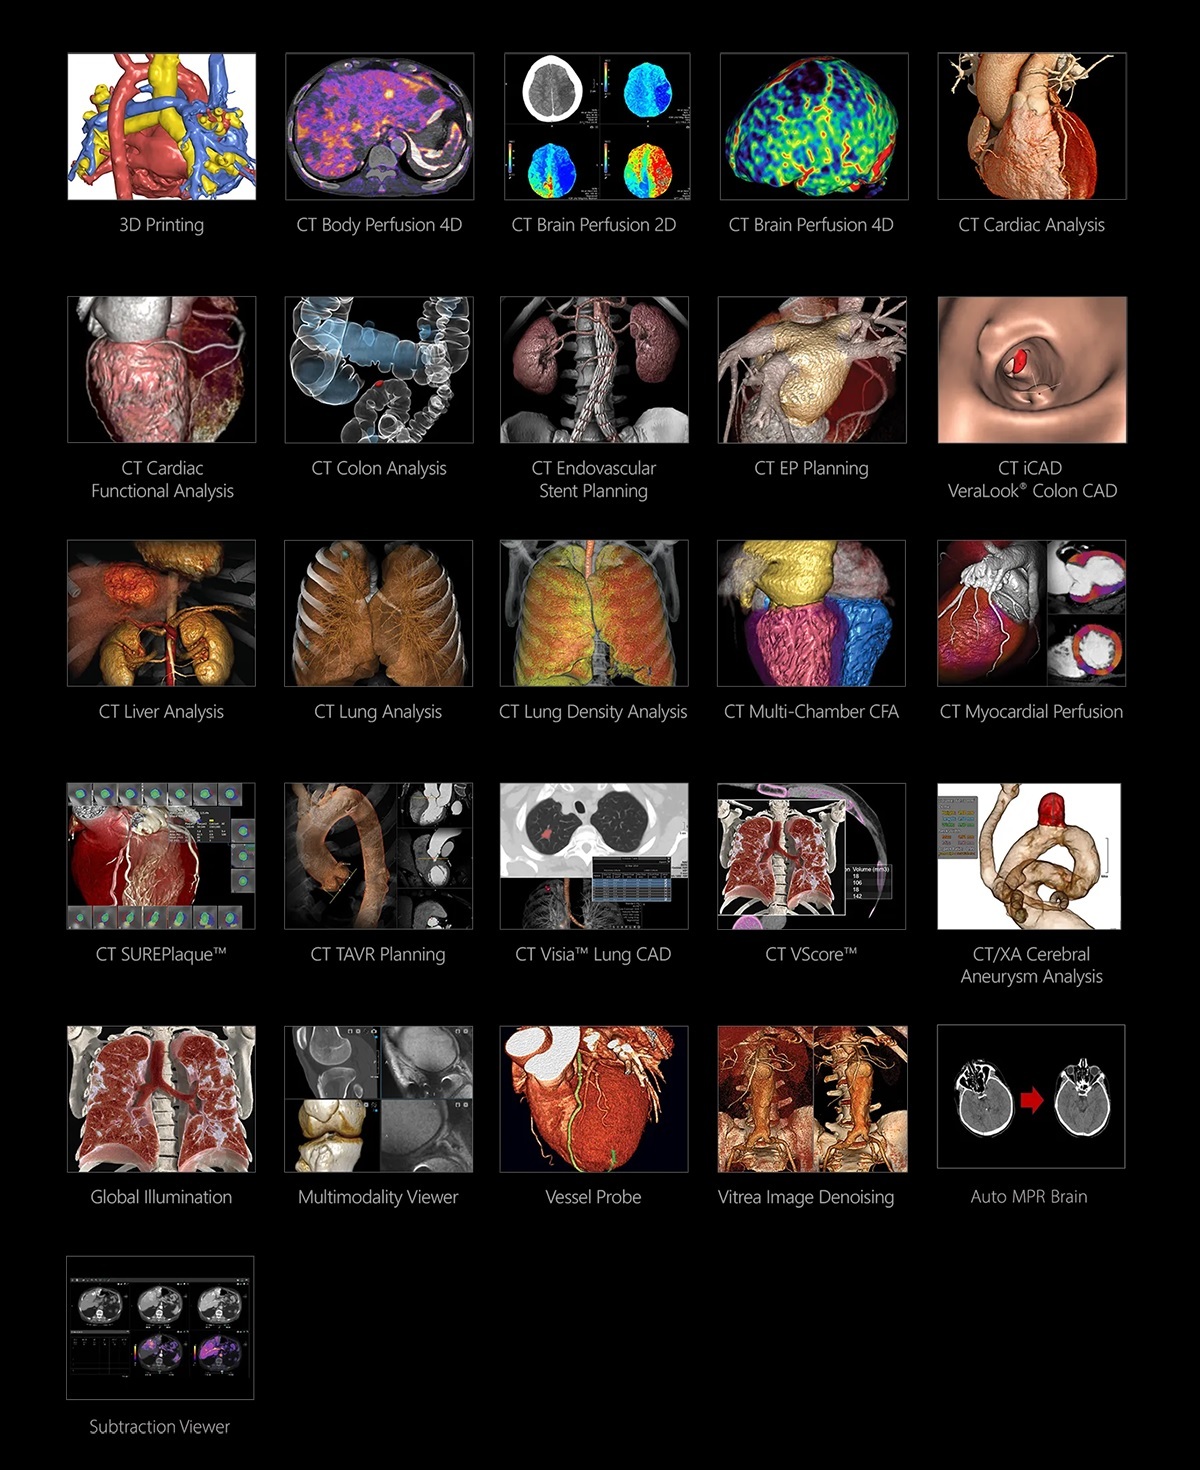

El software Vitrea es un sistema de visualización avanzado multimodalidad que proporciona aplicaciones clínicas completas en una variedad de entornos de las TI.

Las aplicaciones multimodalidad mejoran la confianza diagnóstica en toda la organización. Al proporcionar el acceso a herramientas clínicas avanzadas, el software Vitrea permite a los médicos tener interacciones significativas donde sea que se encuentren.

Las herramientas de imagen avanzadas, como la visualización 3D, en el paquete básico, y las mediciones automatizadas, facilitan la obtención de mejores resultados clínicos mediante el uso de aplicaciones potentes, integraciones optimizadas de desarrolladores de software asociados, soluciones clínicas y flujos de trabajo adaptados a sus necesidades clínicas. Mejores resultados clínicos gracias a potentes flujos de trabajo y aplicaciones de avanzada, perfectamente integradas en la Visualización Avanzada Vitrea.

Global Illumination, renderizado fotorrealista en tiempo real

Áreas clínicas: Oncología, Cardiología, Neurología, MSK / Medicina Deportiva y Salud de la Mujer